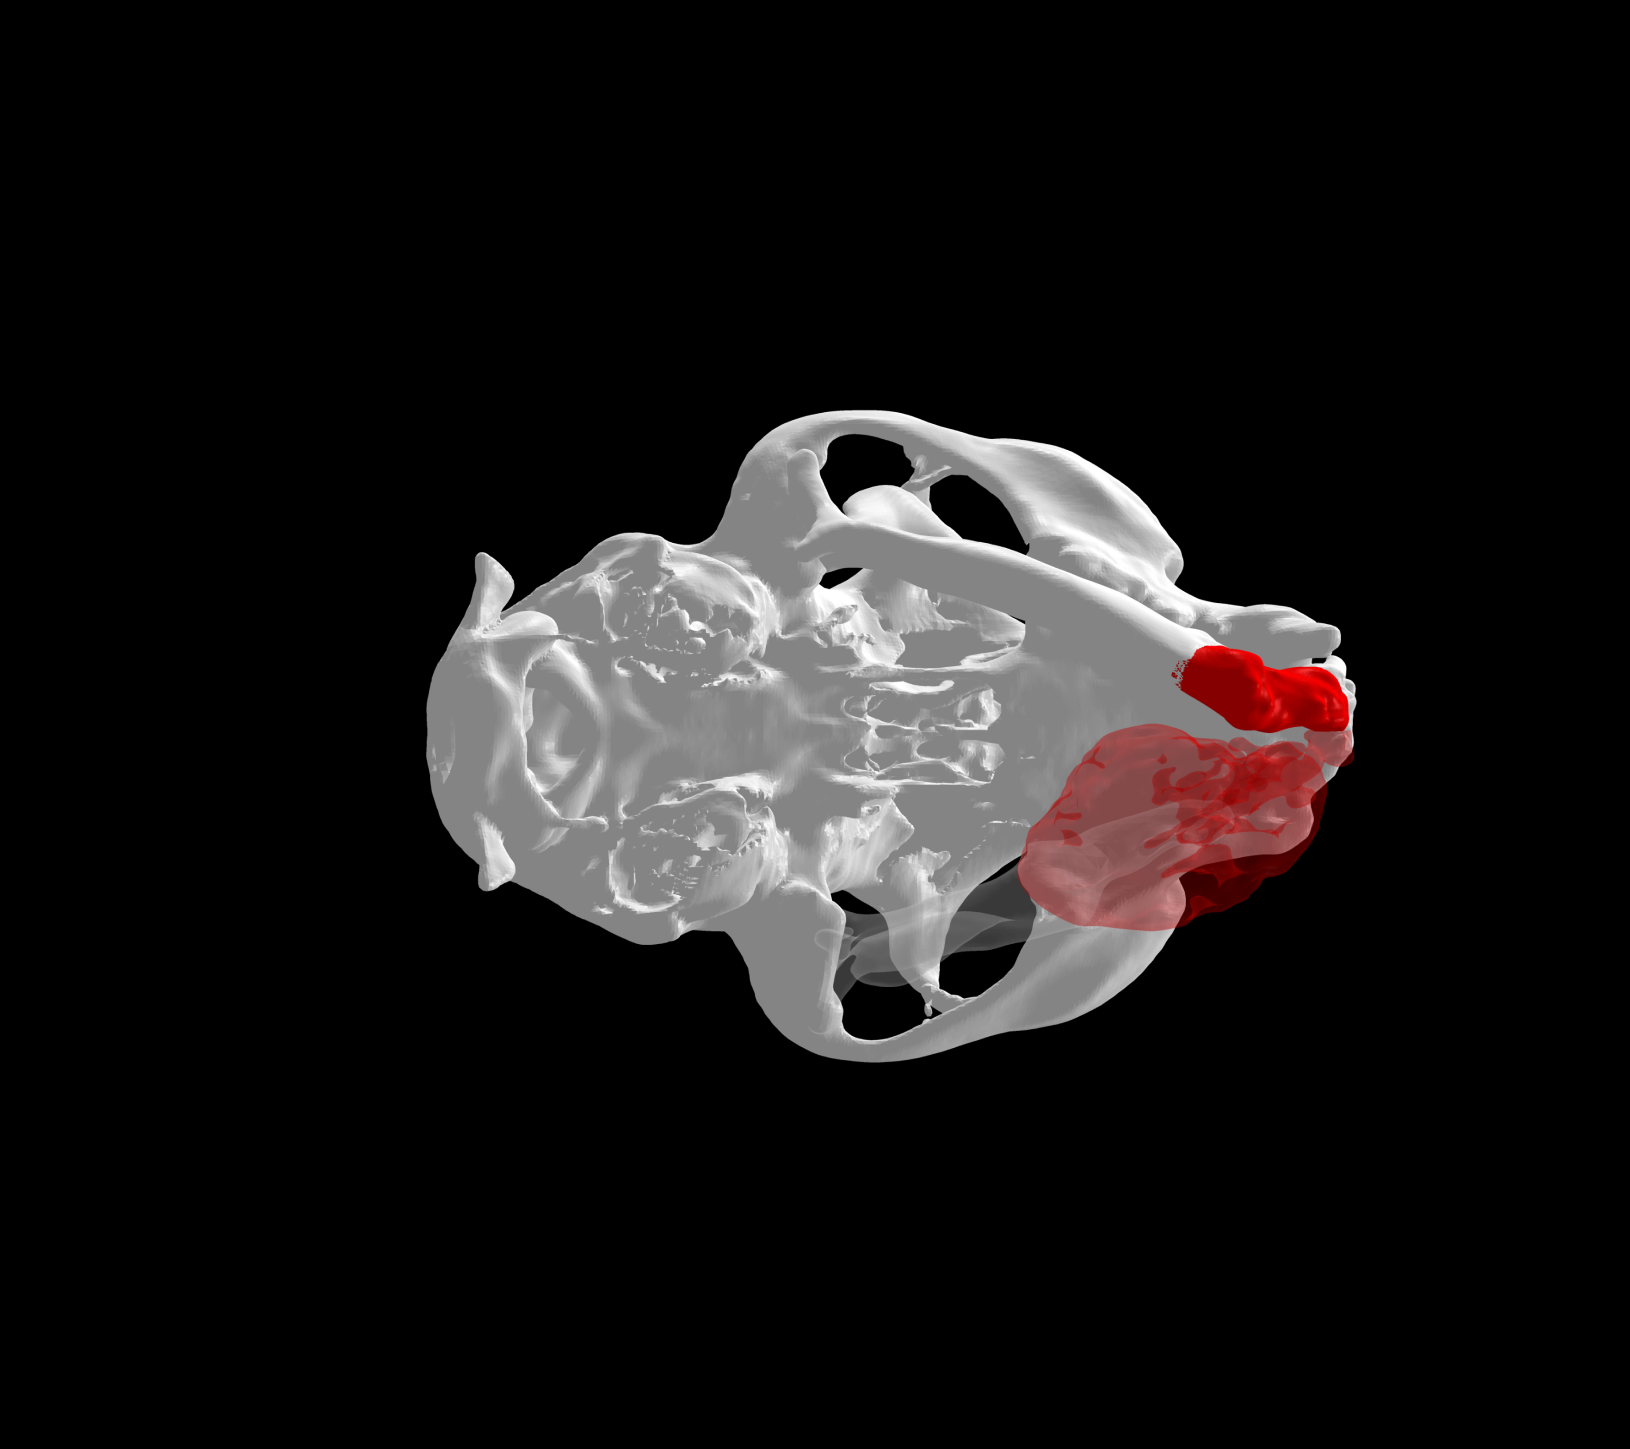

Esto se consigue gracias a los avances en la tecnología de fabricación, como la impresión 3D. Con esta tecnología se pueden crear implantes personalizados tanto en acero quirúrgico como en titanio a partir de imágenes médicas de tomografías computerizadas (TC) o resonancias magnéticas (RM).